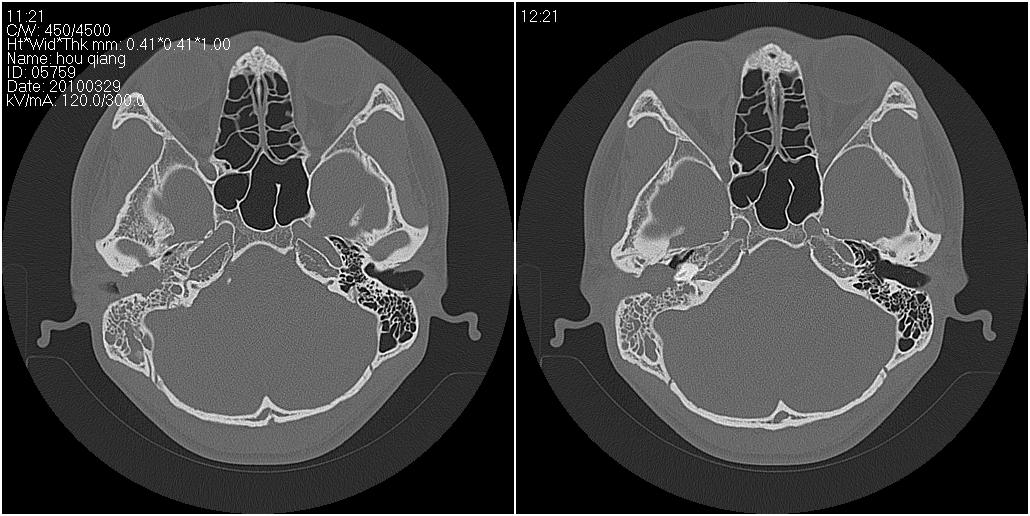

标题: CT25419:男性,18岁。右耳肿、痛5个多月。 [打印本页]

标题: CT25419:男性,18岁。右耳肿、痛5个多月。

1)右侧慢性中耳乳突炎并右侧中耳腔及外耳道肉芽肿或胆脂瘤形成。2)鼻咽腺样体肥大。